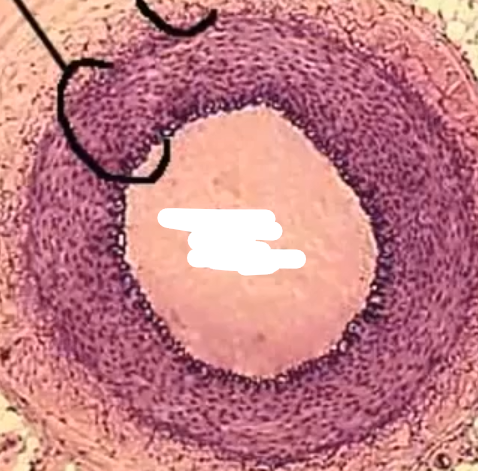

What is this

Vein lumen

What is this

Artery lumen